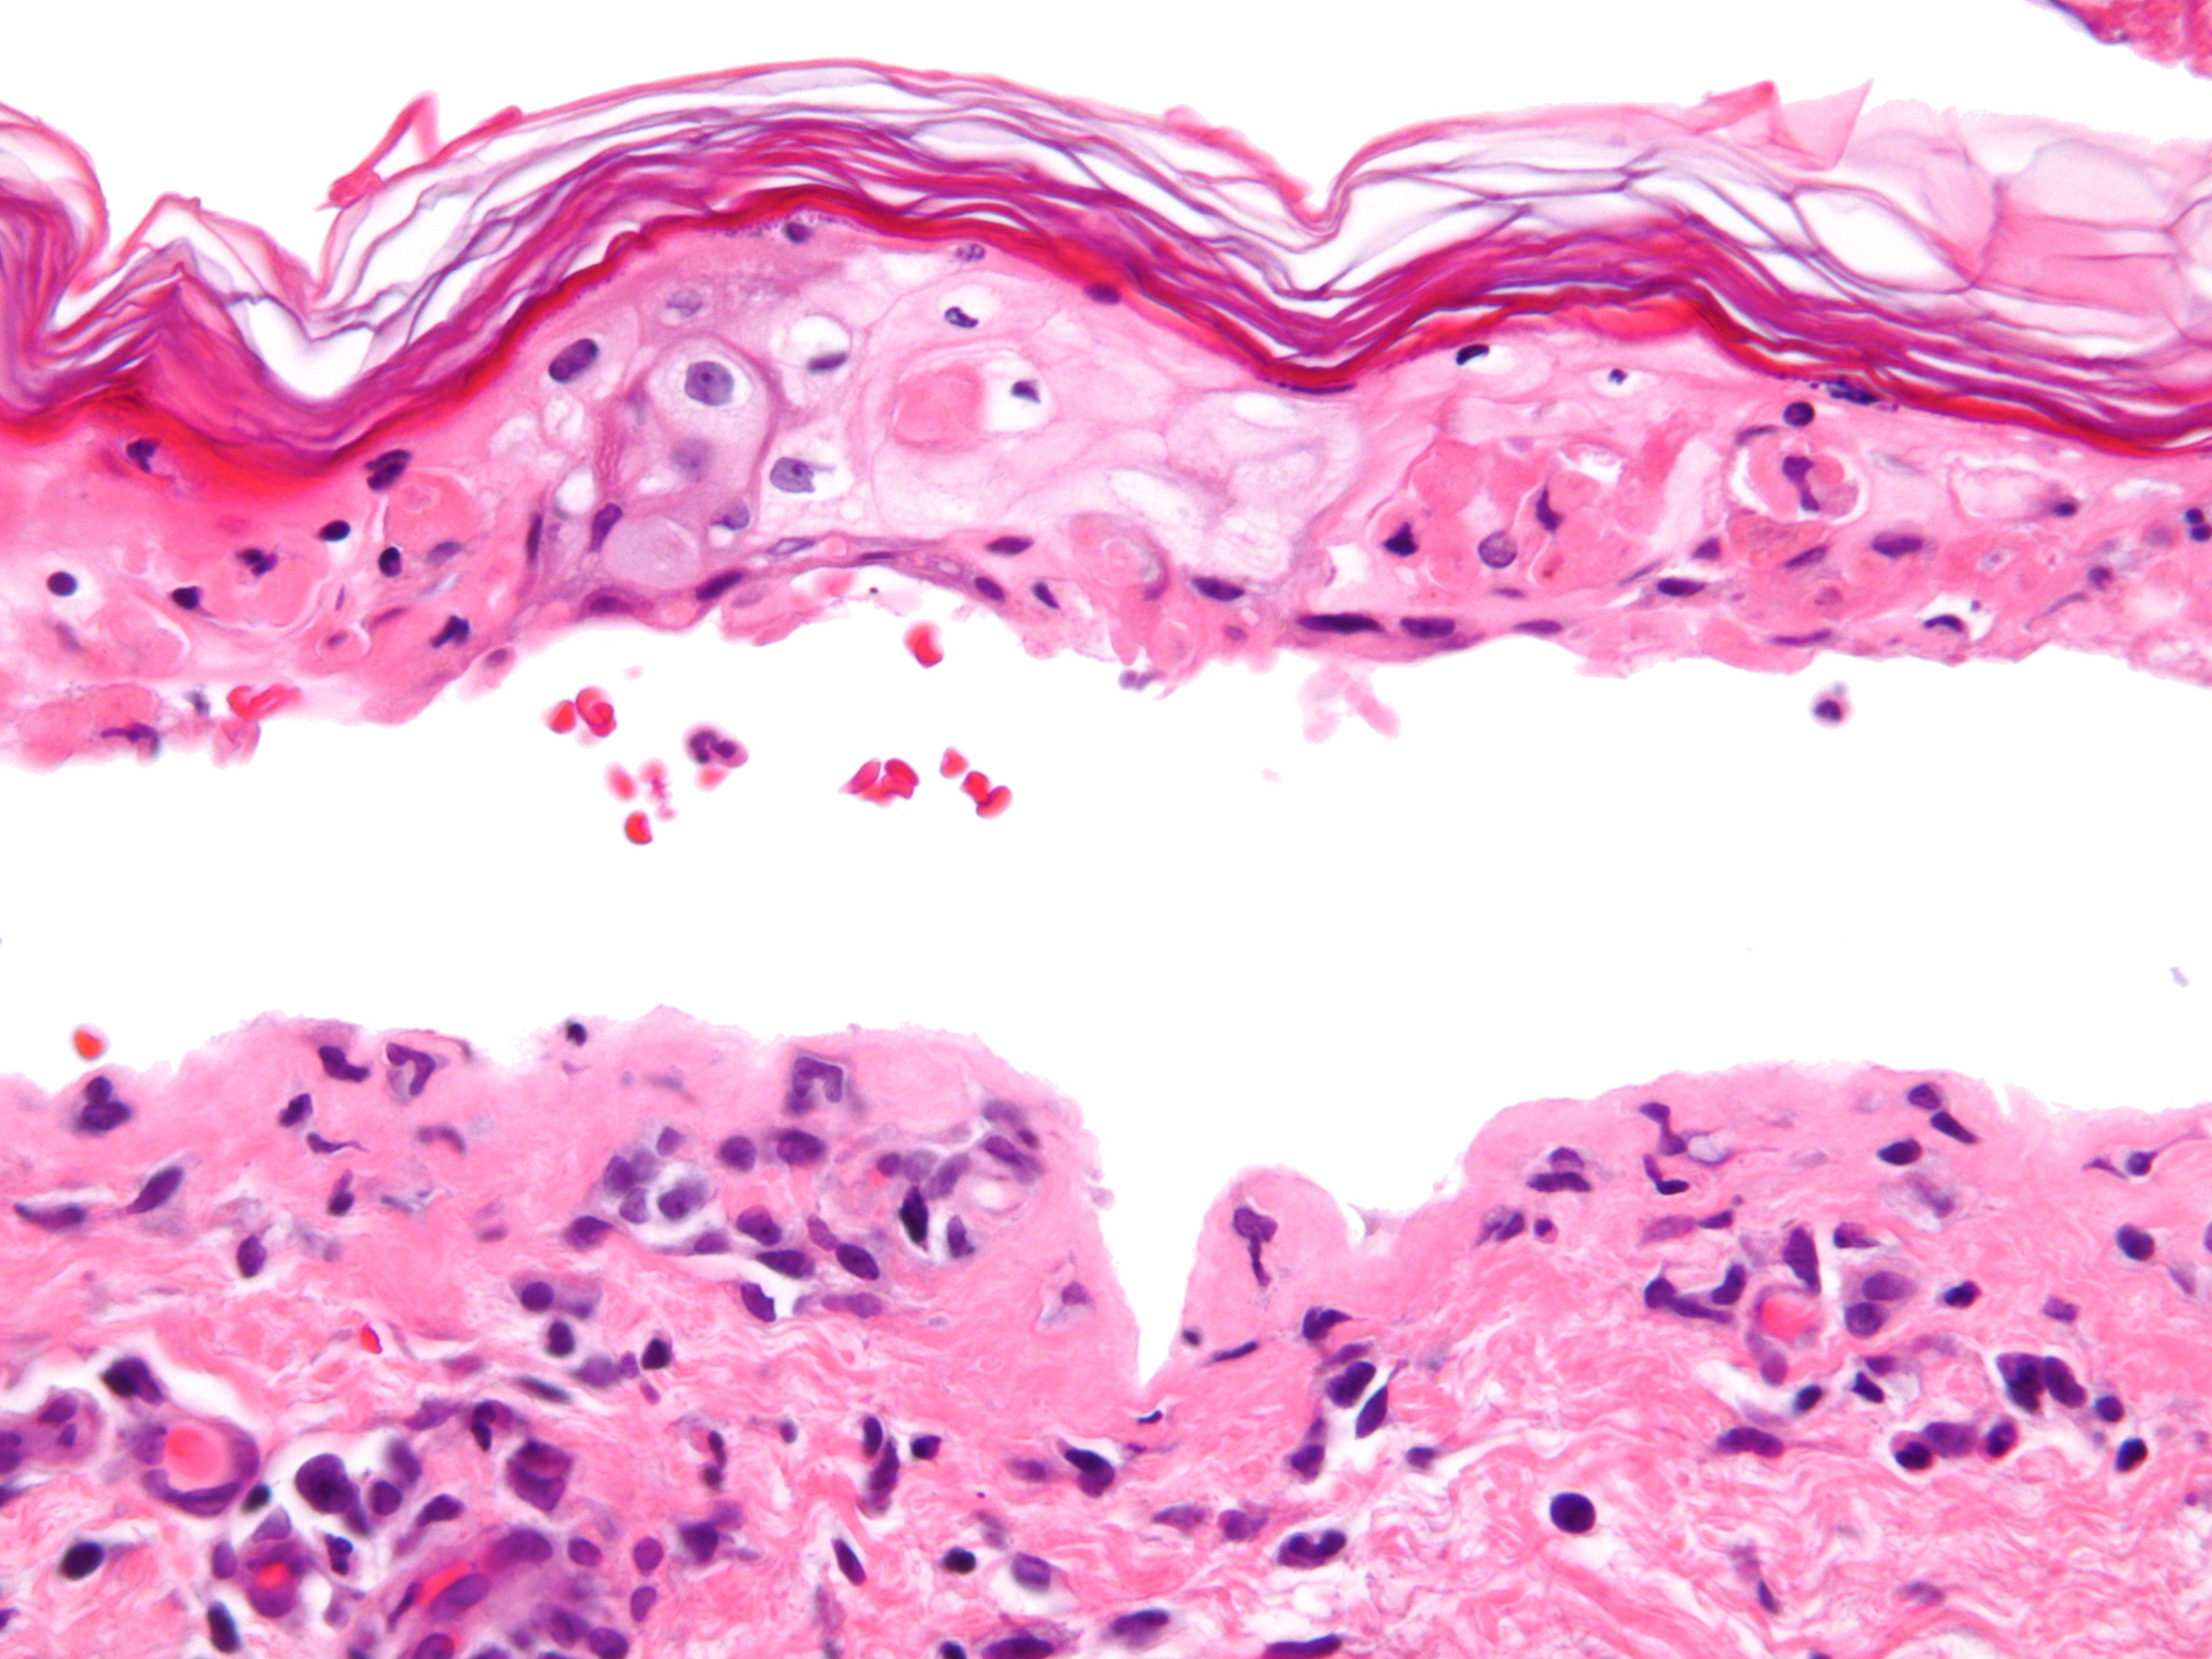

Histologisch

onderzoek: Vroege laesies van SJS en TEN: apoptotische keratinocyten

verspreid in de basale en direct suprabasale lagen van de epidermis. In latere

stadia: sub-epidermale splijting overdekt met confluerend necrose van de gehele

epidermis. Er is een spaarzaam / mild perivasculair ontstekingsinfiltraat, met

name bestaand uit lymfocyten. Immunopathologie: variabele aantallen lymfocyten

(CD 8+) en macrofagen epidermaal, lymfocyten (CD 4+) in de papillaire dermis.

![Toxische epidermale necrolyse (TEN) (click on photo to enlarge) [source: Michael Bonert (Nephron) - Wikimedia - Creative Commons License 3.0] Toxische epidermale necrolyse (TEN)](../../../images/SJS-PA-2z.jpg) |

PA SJS

/ TEN |